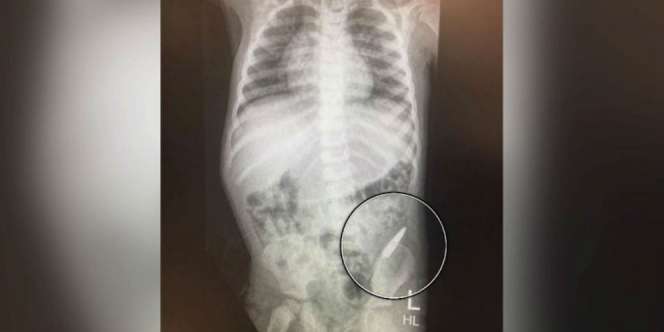

Peluru Bersarang Di Usus Bocah Tiga Tahun Itu (Foto: 9News)

Hunter Wood menelan replika peluru (Foto: 9News)

Hunter dibawa ke rumah sakit. Dari hasil rontgen terlihat peluru itu ditemukan di ususnya.

" Posisi peluru bagus, dan kemungkinan besar itu akan benar-benar keluar tanpa merusak usus," kata Tim.

Pembedahan tidak diperlukan, Hunter hanya harus mengeluarkan proyektil dengan buang air besar. Beruntung, sang ibunya sempat menemukan replika peluru itu.